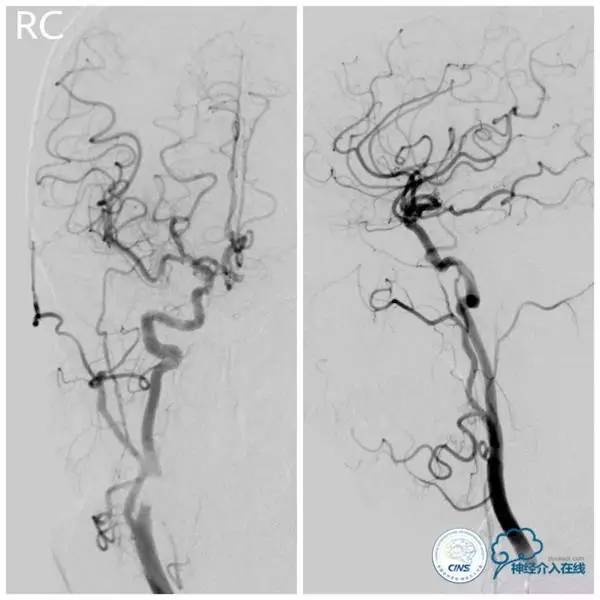

术前造影(图3-6):左椎动脉优势,左椎动脉V4段迂曲,基底动脉近段重度狭窄,双侧胚胎型大脑后动脉。

图3

图4

图5

图6